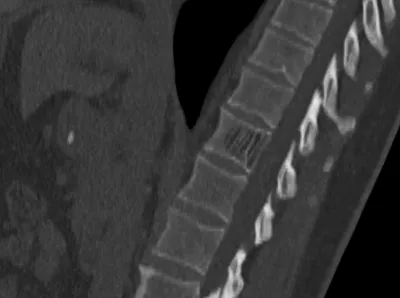

Transverse annulus tear of intervertebral disc

MRISpineAxial+1

4/23/2026